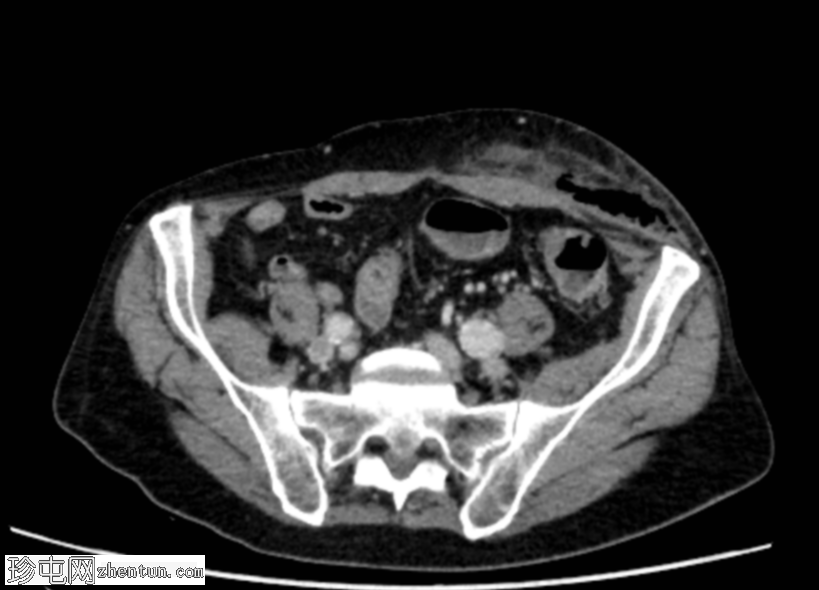

轴向C+门静脉期

疑似乙状结肠憩室炎。左侧直疝,乙状结肠壁一段内有气泡——最有可能是嵌顿疝,憩室穿孔是福尼尔坏疽的病因。

福尼尔坏疽由此沿精索向左半阴囊延伸,并沿腹外斜肌筋膜向头部延伸。